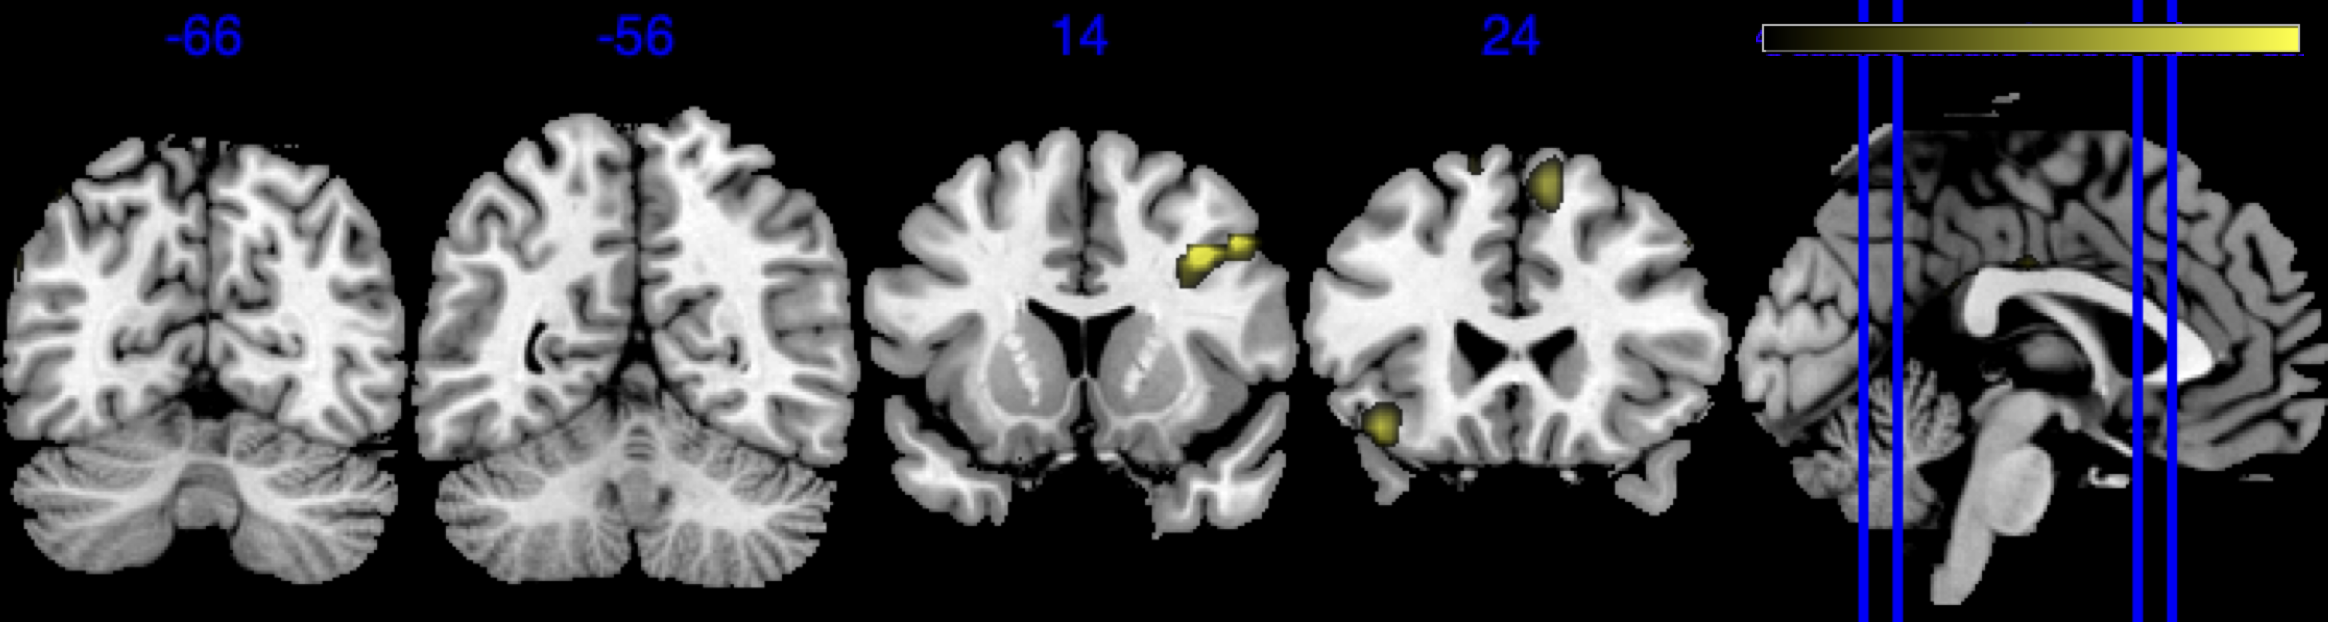

| Negative posterior mean of the spatial mediation effects (color range ) |

![]() |